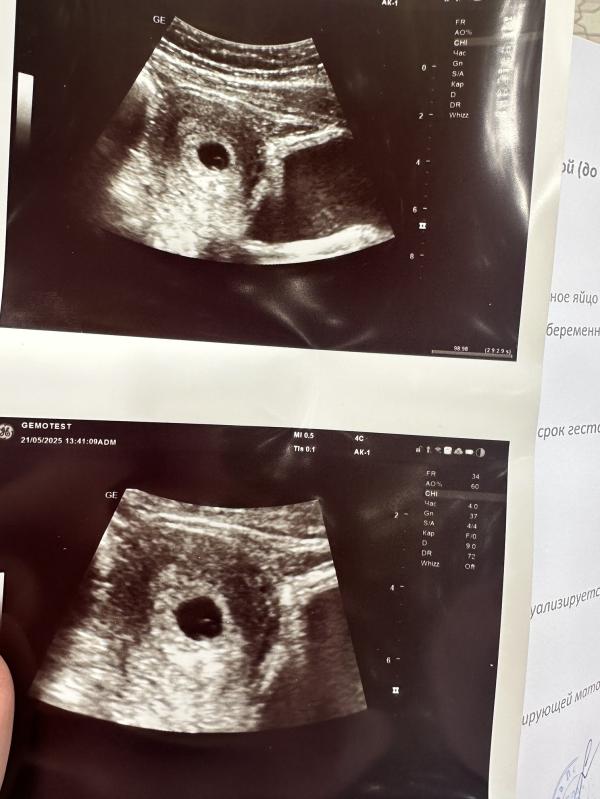

Была повторно на узи, вроде все в порядке❤️❤️❤️ сердечко не услышала, а хотелось🥲❤️

Интересно у меня в заключение пя 11 мм желточный мешочек 3 мм и по узи беременность 5.6 недель. У вас показатели выше и по узи 5.3 😁

@svetaaa92, похоже да, ну главное что все хорошо❤️ у вас сердечко услышали? Пока сказали у меня эмбриона не видно

@millli22, не увидели эмбриона ещё. Вот пойду во вторник повторно к другому узисту